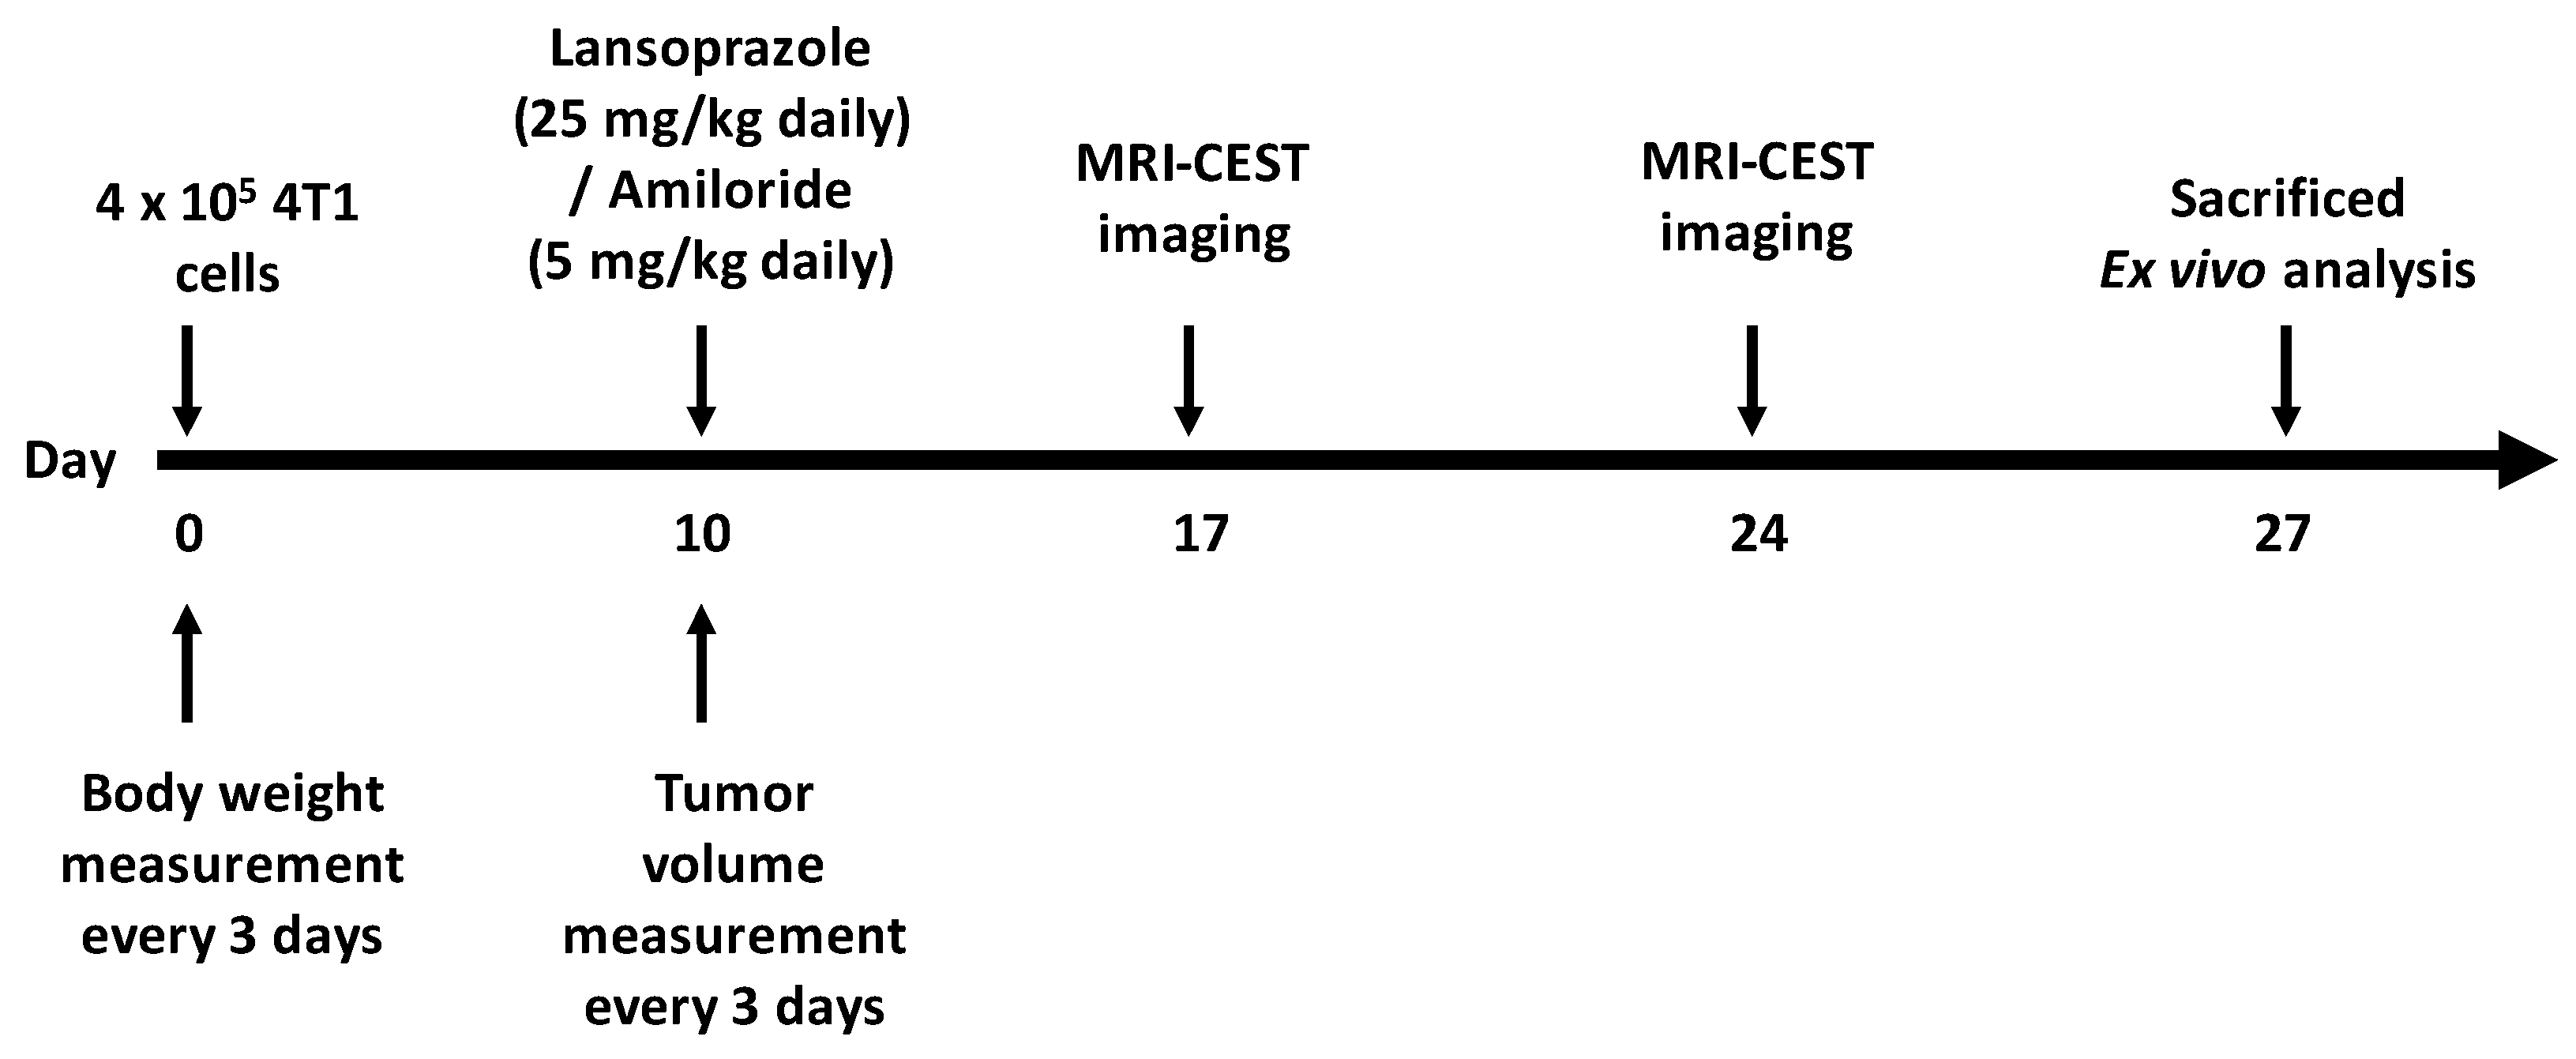

2.6. Tumor Xenograft Animal Model

2.7. MRI-CEST Tumor pH Imaging and Analysis

3.4. Lansoprazole Suppresses the Growth of Breast Carcinoma in Mice

3.5. Lansoprazole Exhibits Increased Extracellular pH In Vivo Assessed through MRI-CEST pH Imaging

3.6. Amiloride Exhibits In Vivo Any Anti-Tumoral Effect and Is Ineffective in Altering Tumor pHe